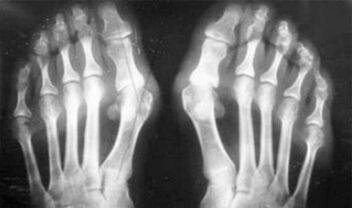

Разликата между артрит и артроза на пръстите и ръцете на ръцете е, че първото заболяване е излекувано, а второто не е така. С артрит се докосва синовиалната обвивка и капсулата на ставата.

Поражението на хрущяла и костната тъкан се случва само в късните етапи в пренебрегвано състояние. С артрозата първо се влияе хрущялната тъкан, а след това костите, възпалението на синовиалната мембрана е от вторичен произход, тоест се развива на техния произход.